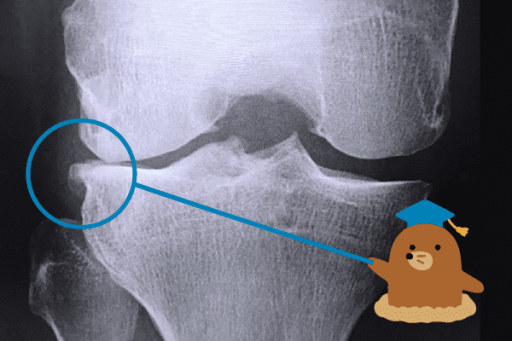

膝關節退化怎麼辦?認識症狀、治療保養方法及注意事項